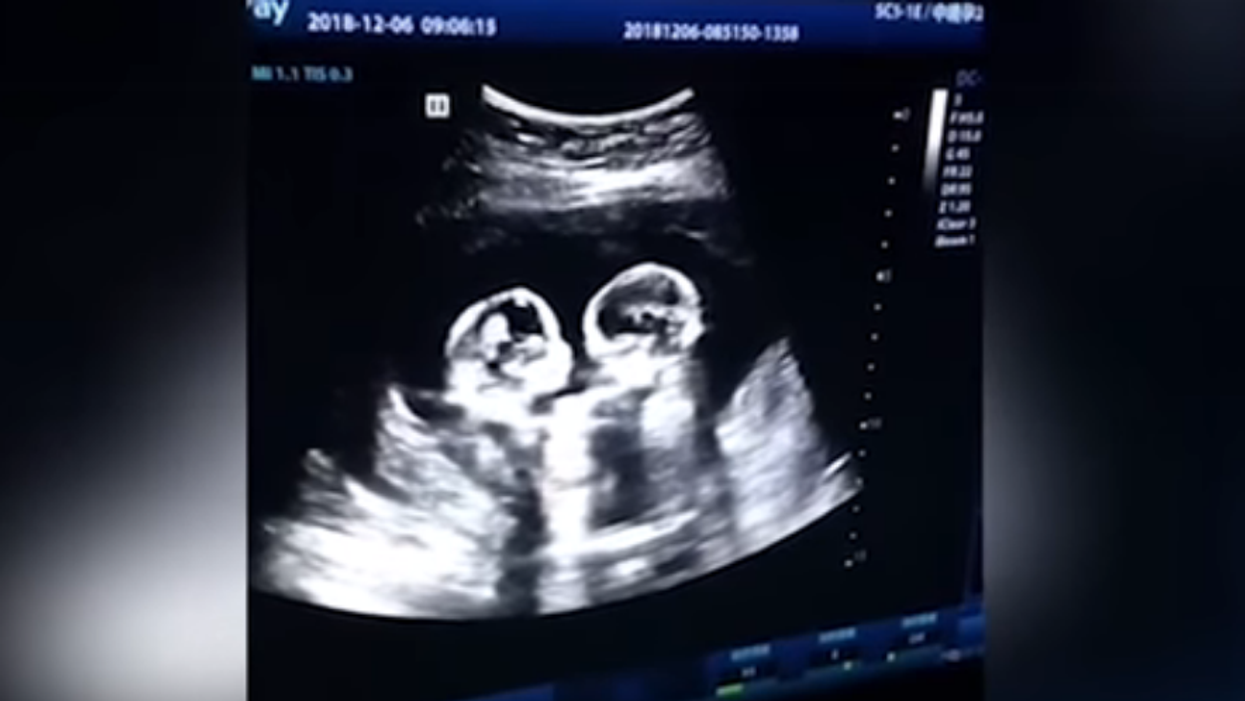

Image source: Let me Trend | YouTube screenshot

According to iHeart Radio, the video from a hospital in China shows a pair of unborn twin sisters who started throwing punches in their mother's womb in December. The two are face to face before one throws the first punch and, well, the rest is fairly easy to predict.

"Monoamniotic twins," or twins who share the same amniotic sac, is a rare phenomenon affecting only a small percentage of twin pregnancies and can be very dangerous. For example, a 2013 news release from Stanford University explained, the children's umbilical cords can become entangled and cut off blood flow.